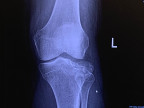

RE: healing from recent fracture surgery

on April 14, 2023 I was in surgery for a comminuted fracture of the lateral left tibia. That’s less than a week ago.

they’ve put me on blood thinners for 12 days. The basic prognosis is no weight-bearing for eight weeks.